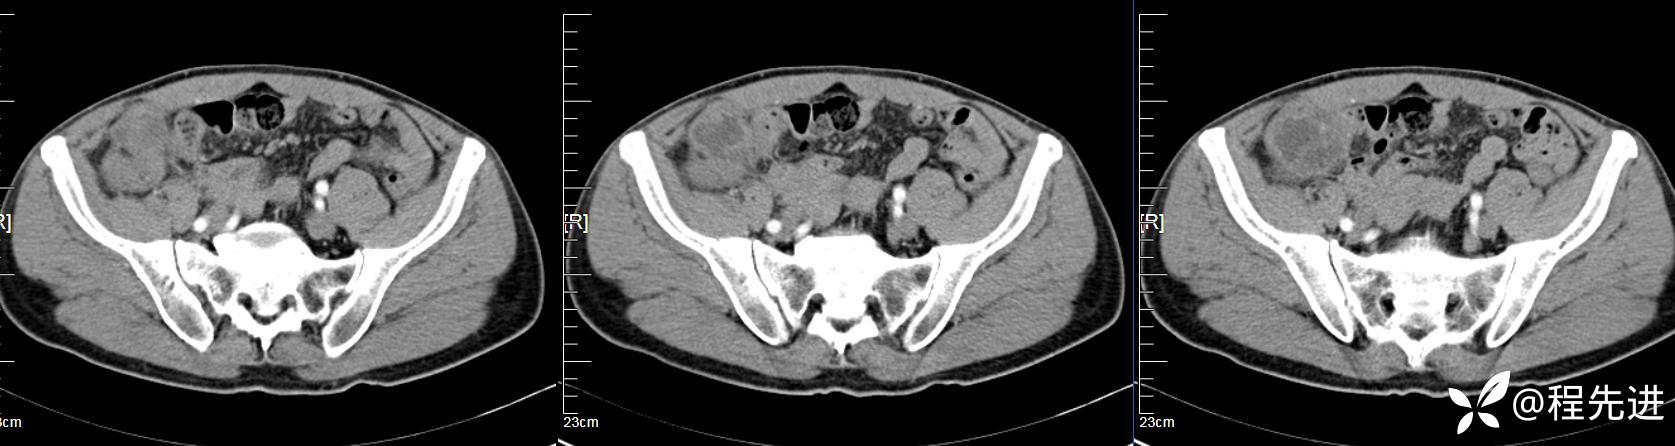

【患者信息】:男,61岁

【现病史及既往史】:右下腹部疼痛伴腹胀2天

【影像检查】